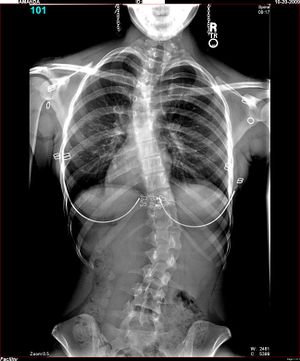

جنف فتاة قوقازية عمرها 16 سنة؛ آشعة سينية أمامية، واقفة، بملابسها

الجنف Scoliosis قوس جانبي يصيب العمود الفقري. وفي معظم الحالات يصبح هذا الوضع ظاهرًا في فترة المراهقة أو قبل ذلك. ويصيب الجنف البنات أكثر من البنين، لكن الأطباء لا يعرفون سببًا لذلك. وقد تؤدي الحالات المتقدمة أيضًا إلى تشوه شديد قد يؤثر في القلب والرئتين والجهاز العصبي. وهذا التشوه يمكن أن يؤدي أيضًا إلى مشاكل نفسية. والأطباء لا يعرفون سبب الإصابة في معظم الحالات، لذلك فإن بعض الحالات تنتج من أمراض في العضلات أو نتيجة تشوهات خلقية عند الميلاد.